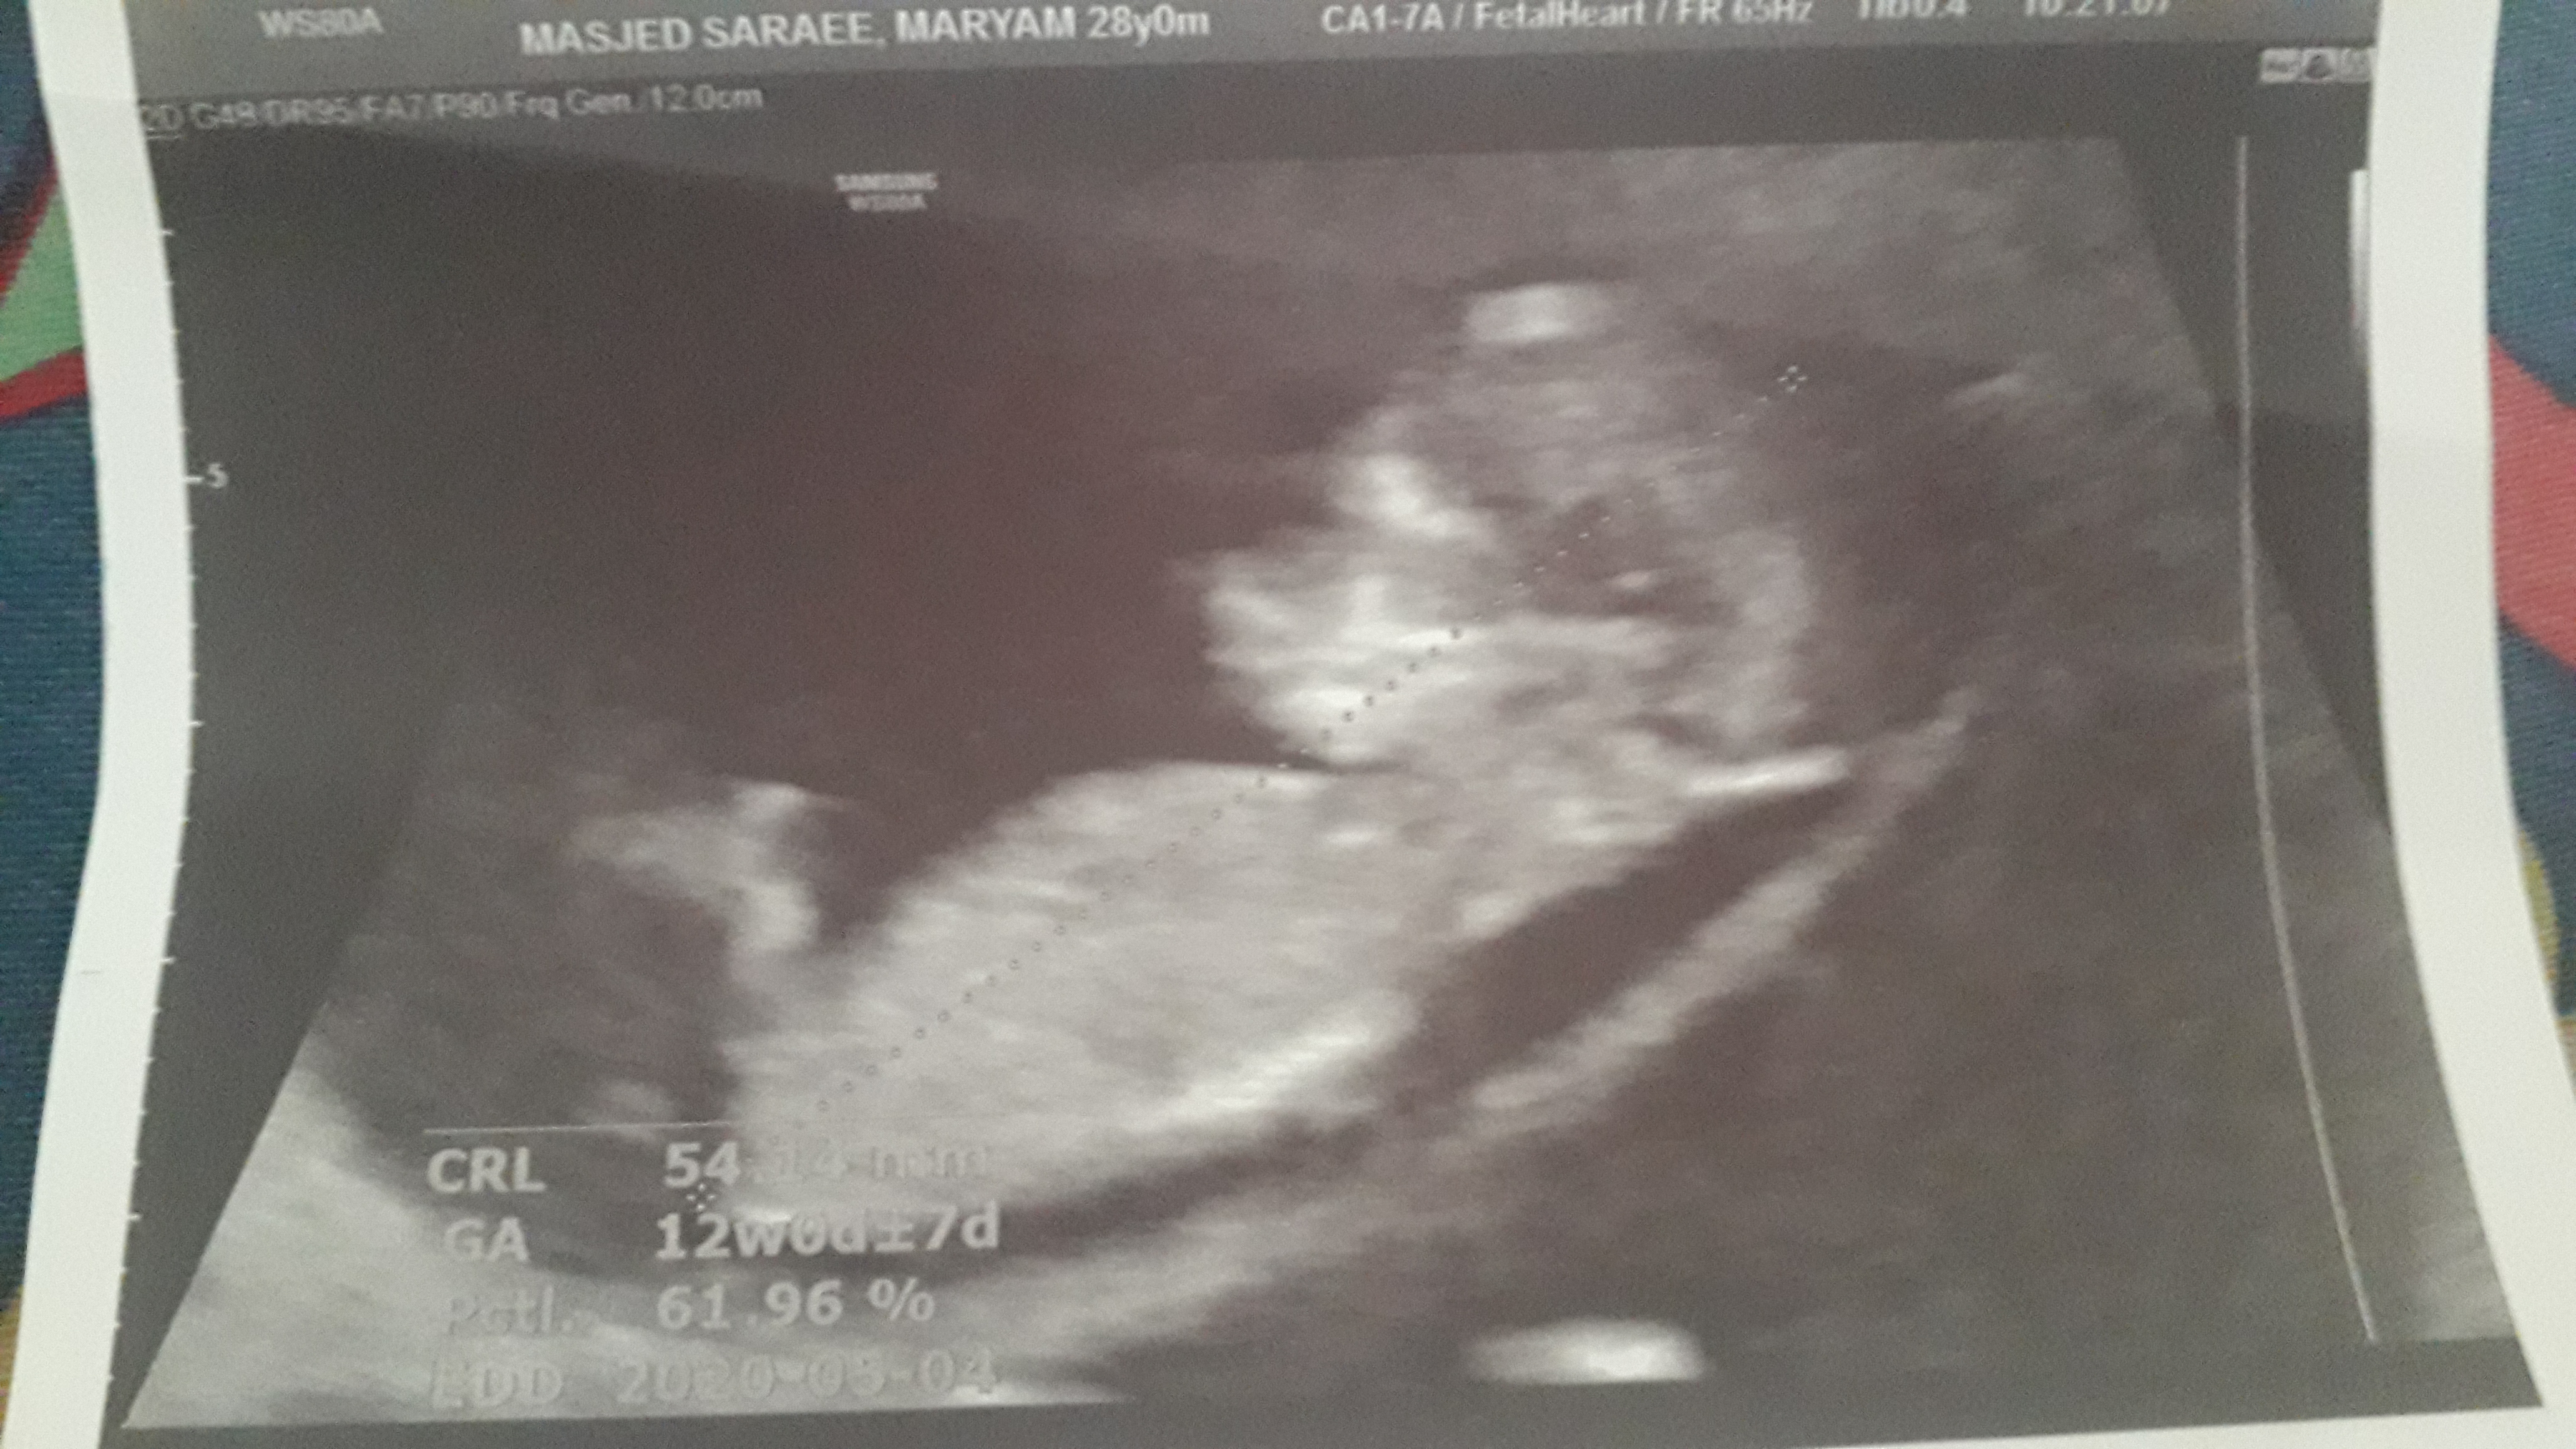

anya_95 عضویت: 1398/05/18 تعداد پست: 1136 ای جانم دوقلو😍فک کنم هردو دخترن ولی عکس دومیو یکم شک دارم ❤میشه واسه سلامتی گل پسرم ی صلوات مهمونم کنی❤مرسی مهربونا😘